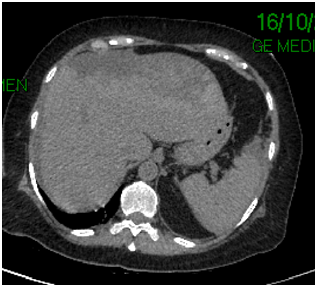

68-year-old female with presence of secondary hypothyroidism 8 years of evolution in treatment with levotiroxin, systemic hypertension 2 year of evolution treated with losartan, thyroidectomy 8 years ago, c-sections 243 and 38 years ago, the patient denies the use of alcohol or tobacco. Initiates with sudden transitive pain in epigastrium, vomiting several times, undergoing imaging and laboratory tests diagnosing pancreatitis its determined that the patient is in need of a ERCP, which is performed at a private institution, during the procedure the major duodenal papilla is identified anatomically normal but without bile output with multiple cannulation attempts (Figure 1), continuing with procedure applying contrast appreciating two gallstone suggesting images in distal choledocus which measures 9 mm in diameter (Figure 2) with a probable stenotic area in the distal portion, a wide sphincterotomy is performed with posterior passing of extraction balloon doing multiple sweeps obtaining two 7 mm gallstones due to said area of stenosisa 10 fix 10 cm stent is placed towards the right hepatic duct. After the procedure the patient presents moderate to intense pain in right hypochondrium alongside hypotension, administrating crystalloids and vital sing stabilization ordering CT scan where a sub capsular collection is visualized, varying heterogenicity from 600 to 20 HU, highly suggestive of a serohematic component with approximate size of 17 by 13.8 by 6.5 cm, with approximate volume of 820 cc (Figure 3) (Figure 4) with diagnosis of a probable subcapsular hematoma, with later presentation of acute kidney failure requiring temporary renal substitution therapy, once she was hemodynamically stable its moved to our unit to continue treatment, taking laboratory exams determining hyperbilirubinemia, due to conjugated bilirubin and elevated liver enzymes, deciding to do new CT scan where a 20% diminution of hematoma size is appreciated and adding pleural effusion to the findings deciding to give a conservative management, eight days later performing control ultrasound finding hematoma with a tendency to re absorption .

Figure 4 Axial tomography showing the hepatic hematoma.